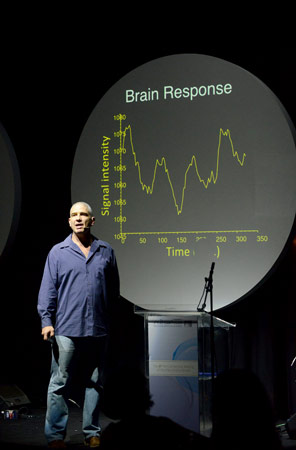

সম্প্রতি কলকাতায় তাঁর এক পারিবারিক বন্ধুর কাছে ঘুরতে এসেছিলেন সবেল। আনন্দবাজারকে বললেন, ‘‘আমরা দীর্ঘ দিন ধরে গবেষণা করছি চোখের জল নিয়ে। একেবারে হালে আমরা গবেষণায় দেখেছি, মানুষের চোখের জল সব সময়েই রাসায়নিক বার্তা বা সংকেত (কেমিক্যাল সিগন্যাল) বয়ে নিয়ে বেড়ায়। কোনও মহিলার চোখে জলে থাকা ‘ফেরোমোন’ সামনে দাঁড়ানো কোনও পুরুষের শরীরে টেস্টোস্টেরন হরমোনের ক্ষরণের পরিমাণ কমিয়ে দেয়। সেই পুরুষের যৌন উত্তেজনাকে প্রশমিত করে বা তাকে যতটা সম্ভব কমানোর চেষ্টা করে বা কমিয়ে দেয়। সেই গবেষণাপত্রটি ছাপা হয়েছে বিজ্ঞান-জার্নাল ‘সায়েন্স’-এ।

নিউরো-বায়োলজিস্ট নোয়াম সবেল

সহযোগী ভারতীয় গবেষক অনিতা সারেঙ্গির কথায়, ‘‘চোখের জল আমাদের ‘মুড’ কী ভাবে কতটা বদলে দেয়, মস্তিষ্কের স্নায়ুর কোন কোন কার্যকলাপ তাদের নিয়ন্ত্রণ করে, ক্ষরণের আগে নিউরনগুলি কী ভাবে চোখের কোষ, কলাগুলিকে ‘সিগন্যাল’ বা সংকেত পাঠায়, নারী ও পুরুষের চোখের জলের ফারাক কতটা, কতটা পার্থক্য থাকে তাদের রাসায়নিক উপাদানে, প্রচণ্ড খিদেয় কেন চোখে জল আসে, আবেগ-সঞ্জাত (ইমোশনাল) ও আবেগ-বিবর্জিত (নন-ইমোশনাল) চোখের জলের ফারাকটা কোথায় আর সেই ফারাকটা হয় কেন, এ সব বুঝতে সহজ করবে চোখের জলের ব্যাঙ্ক। কারণ, গবেষণার জন্য তখন চোখের জল পেতে অসুবিধা হবে না।’’

সবেল বলছেন, ‘‘আমরাই প্রথম দেখিয়েছি, চোখের জলের মাধ্যমে মানুষ তার সঙ্গী, পরিচিত, কম পরিচিত বা অপরিচিতের সঙ্গে রাসায়নিক ভাবে যোগাযোগ (কেমিক্যাল কমিউনিকেশন) গড়ে তোলে। এটাকেই বলে ‘কেমো-সিগন্যাল’। যাতে কোনও গন্ধ থাকে না। তবে তা লবণাক্ত। এর আগে ওই ‘কেমো-সিগন্যাল’ একমাত্র ব্লাইন্ড মোল র্যাট-এই পাওয়া গিয়েছিল। যদিও শিশু ও পুরুষের চোখের জল কোনও ‘কেমো-সিগন্যাল’ পাঠায় কি না, সে ব্যাপারে এখনও নিশ্চিত নই আমরা। তবে আমরা দেখেছি, ইমোশনাল চোখের জলে অনেক বেশি প্রোটিন থাকে। চোখ ভাল রাখার জন্য সাধারণ চোখের জলে অতটা পরিমাণে প্রোটিন থাকে না। এই প্রোটিন আমাদের বগলেও থাকে। আমরা এও দেখেছি, পুরুষের ঘামের গন্ধ নারীদের সেই পুরুষের প্রতি যৌন আসক্তিকে বাড়িয়ে তোলে। সেই ঘামের গন্ধ বিভিন্ন পুরুষের ক্ষেত্রে বিভিন্ন রকমের হয়। এমনকী, পুরুষের বিভিন্ন ‘মুডে’ সেই ঘামের গন্ধও হয় নানা রকমের। দেখা গিয়েছে, সদ্য মা হওয়া নারীর বক্ষ আবরণী বা জামাকাপড়ের গন্ধ অন্য নারীর (যিনি মা হননি বা আসন্নপ্রসবা নন) যৌন উত্তেজনা বাড়িয়ে দেয়।’’